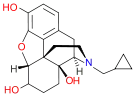

Oripavine derivatives

Thienorphine

- 7-PET

- Acetorphine

- Alletorphine (N-allyl-noretorphine)

- BU-48

- Buprenorphine

- Buprenorphine-3-glucuronide

- Cyprenorphine

- Dihydroetorphine

- Etorphine

- Homprenorphine

- 18,19-Dehydrobuprenorphine (HS-599)

- N-cyclopropylmethylnoretorphine

- Nepenthone

- Norbuprenorphine

- Norbuprenorphine-3-glucuronide

- Thevinone

- Thienorphine

Structures

| Oripavine derivatives | ||||

|---|---|---|---|---|

7-PET 7-PET |

Acetorphine Acetorphine |

Alletorphine Alletorphine |

BU-48 BU-48 |

Buprenorphine Buprenorphine |

Cyprenorphine Cyprenorphine |

Dihydroetorphine Dihydroetorphine |

Etorphine Etorphine |

Homprenorphine Homprenorphine |

18,19-Dehydrobuprenorphine 18,19-Dehydrobuprenorphine |

N-cyclopropylmethylnoretorphine N-cyclopropylmethylnoretorphine |

Nepenthone Nepenthone |

Norbuprenorphine Norbuprenorphine |

Thevinone Thevinone |

Thienorphine Thienorphine |